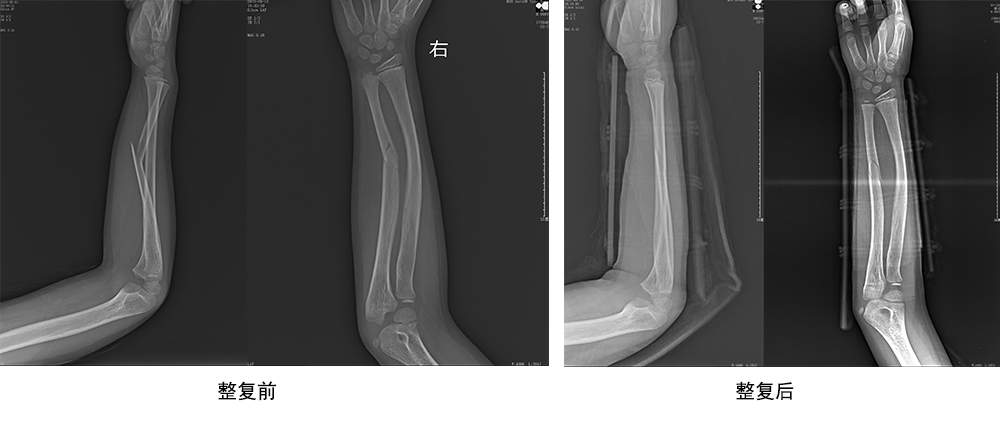

傳統(tǒng)手法整復病例影像

CR99142